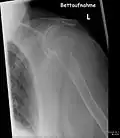

- Vues de fractures pathologiques

Fracture pathologique de l'humérus sur une métastase de carcinome du rein

Fracture pathologique du bras gauche sur une métastase osseuse de cancer du sein